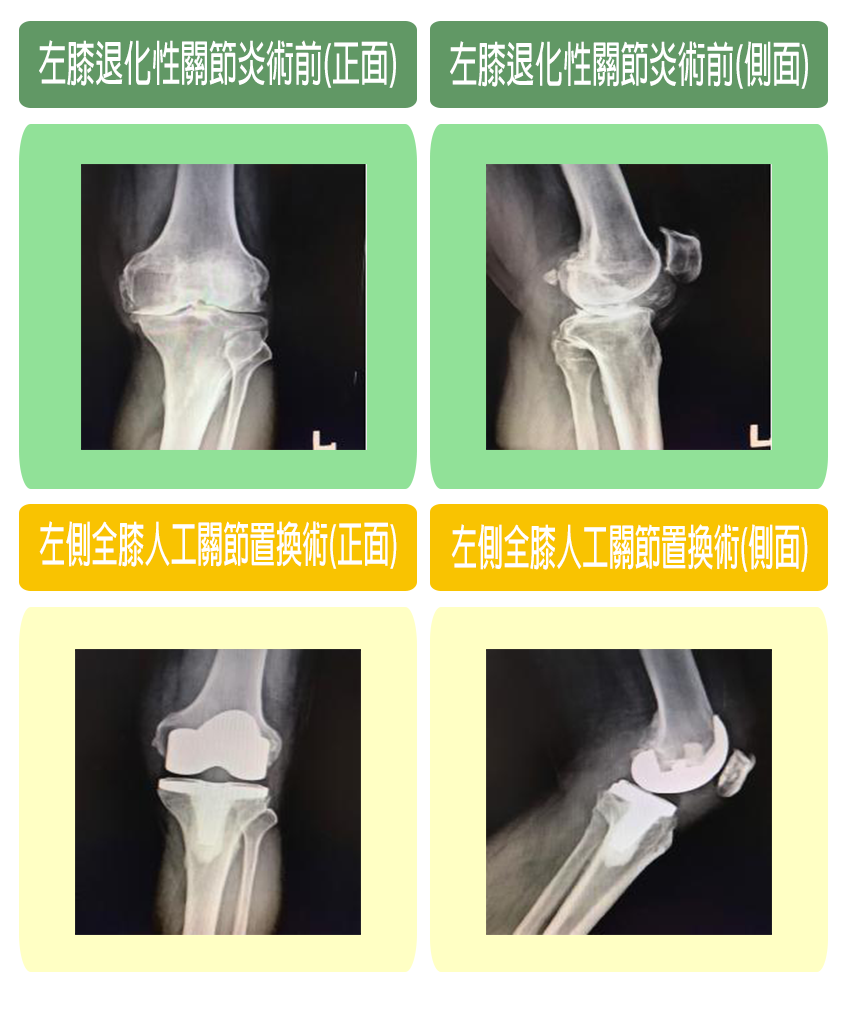

人工膝関節置換術 Total Knee Arthroplasty 全人工膝(ひざ)関節置換術(Total Knee Arthroplasty:TKAの詳細情報

全人工膝(ひざ)関節置換術(Total Knee Arthroplasty:TKA。COPYRIGHT UNION HOSPITAL 手術資料。Total knee replacement surgery (TKA) - Stock Illustration。人工膝関節置換術に関する専門的な内容を網羅した書籍。。关节置换术(膝关节置换)| 伊丽莎白医院。- タイトル: 人工膝関節置換術- サブタイトル: Total Knee Arthroplasty- 出版社: 南江堂- 定価: 1800円ご覧いただきありがとうございます。